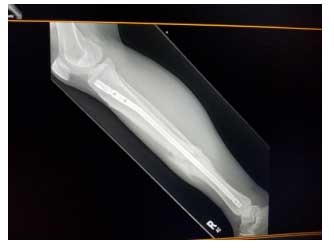

Open Tibial Fractures; The tibia (shinbone) is a subcutaneous bone, meaning that there is little fat between the bone and skin; therefore, tibia fractures are often open. Meaning, the bone breaks and punctures through the skin. Tibia fractures are a medical emergency because the injury causes the patient to be more susceptible to systemic infections and can delay bone healing! The treatment goal is to save the life of the patient and the limb, mend the fracture, and prevent infections. Although this is a severe injury, a speedy recovery is possible.

● Routine limb, chest, and cervical (neck) X-rays will be ordered.

Creative Endeavors. (2022). [X-ray]. Right tibial fracture with internal fixation hardware. https://www.shutterstock.com/image-photo/right-tibial-fracture-internal-fixation-hardware-2156433527